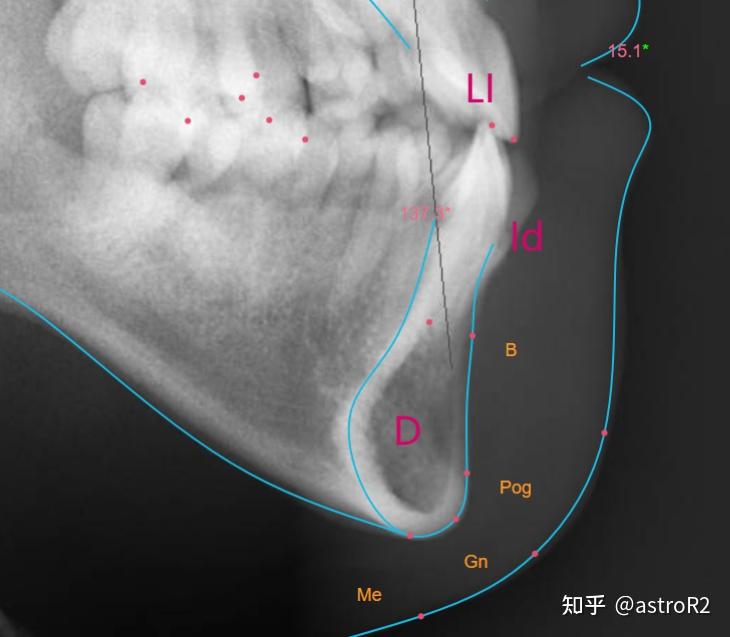

口腔医生须知:头影测量分析 - 知乎

口腔医生须知:头影测量分析